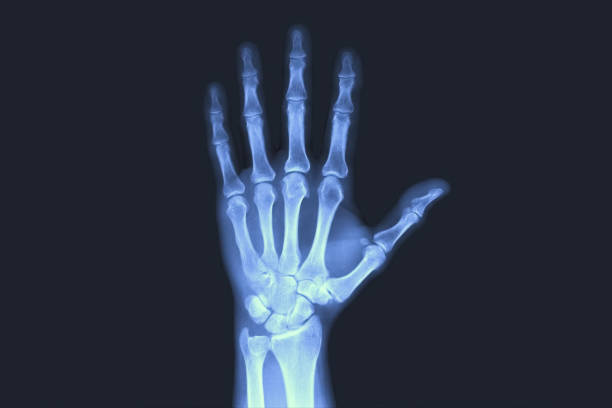

💪Hand Injuries in Basketball: Jammed Fingers, Dislocations, and When to Worry

Common Types of Hand Injuries in Basketball

Finger Fractures

A fracture is a break in the bone.

These are often mistaken for “just a jammed finger” early on.